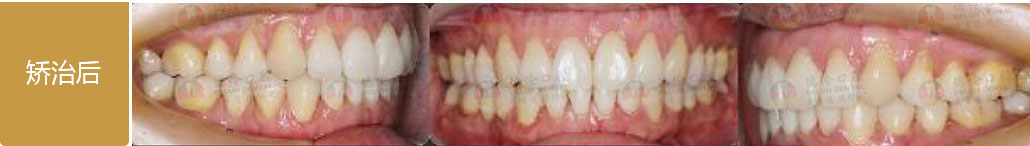

骨性I類,均角,安氏I類

上牙列重度擁擠,下牙列輕-中度擁擠

上中線右偏

13唇側錯位

• 【治療方案】

拔除14,排齊上牙列

下頜尖牙適當擴弓,配合適量鄰面去釉,排齊下牙列

上頜左側配合適量鄰面去釉,調整中線

盡量調整后牙為尖窩咬合關系

矯治前后對比

蛻變周期:上頜16個月,矯治效率提升30%,下頜12個月,矯治效率提升20%